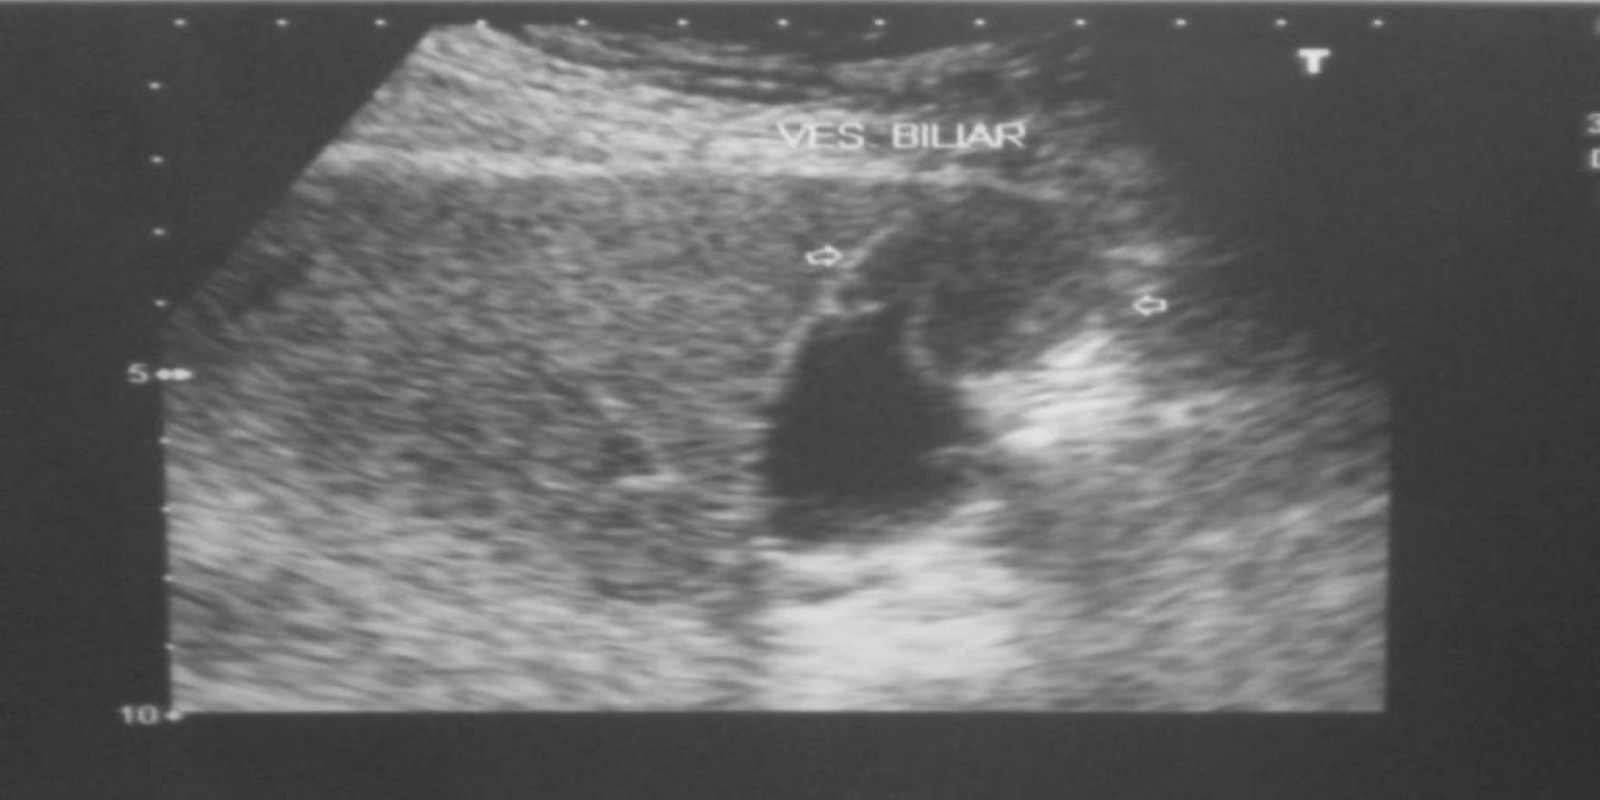

Caso Código 025A de Câncer da Vesícula Biliar

Cod.: 025A